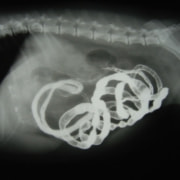

・レントゲン検査:腸内ガス陰影重度

・バリウム像影検査:造影後2時間、胃からのバリウム排泄なし上記検査結果より、内視鏡検査実施。

・内視鏡検査結果:胃内炎症性病変あり。胃の幽門部から十二指腸領域に向かいヒモ状異物確認。

内視鏡検査結果より、十二指腸領域へのヒモ状異物の可能性があるため、同日腸内異物摘出術実施。

腸内異物摘出術

腸管のアコーディオン様所見

腸内異物摘出

摘出した異物

今回の様なヒモ状の異物は、腸の蠕動運動により腸管を傷つけ、発見が遅れると腸穿孔などの重篤な状態を引き起こします。本症例は、術後1週間程で回復し、現在の経過は良好です。